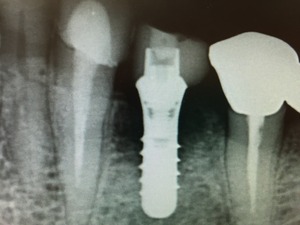

今回の症例はストローマンインプラントSLActiveで行った症例で骨が増えたものをお見せします。

このインプラントは不思議な特性があります。インプラントの周囲に最初は骨が少なくてもまとわりつくように増えるケースをいくつか経験しています。それゆえにロストした症例はいまのところ1つもありません。こんなインプラントならドクターも患者さんも安心ですね!